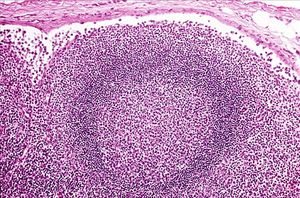

若把癌細(xì)胞比喻為出征的軍隊(duì),而我們身體的淋巴結(jié)就像是將被癌細(xì)胞攻擊的一座座堡壘,那么前哨淋巴結(jié)將是癌細(xì)胞軍隊(duì)出征路線上第一座防御關(guān)卡。如果癌細(xì)胞軍隊(duì)尚未侵犯這第一座堡壘,我們就可以推測(cè)接下來的淋巴結(jié)也尚未遭到癌細(xì)胞軍隊(duì)的攻擊。因此,手術(shù)時(shí)取下前哨淋巴結(jié)檢查是否有癌細(xì)胞侵犯,可以做為腋下淋巴結(jié)是否已經(jīng)受到癌細(xì)胞轉(zhuǎn)移的指標(biāo),用於確定癌癥疾病分期,并做為日后后續(xù)化學(xué)治療的參考;并且也可以避免不必要的腋下淋巴廓清手術(shù)。

前哨淋巴結(jié)攝影可幫助外科醫(yī)師精確定位前哨淋巴結(jié)進(jìn)行切片。若前哨淋巴結(jié)沒有腫瘤侵犯,就不需要再接受大范圍的淋巴廓清術(shù)。這樣一來,對(duì)於早期惡性腫瘤的患者而言,手術(shù)時(shí)間大幅變短、出血少、傷口小,并可減少因淋巴結(jié)摘除而產(chǎn)生淋巴水腫或其他并發(fā)癥的情形。且前哨淋巴結(jié)病理檢驗(yàn)結(jié)果可供醫(yī)師進(jìn)行進(jìn)一步的治療評(píng)估計(jì)畫。